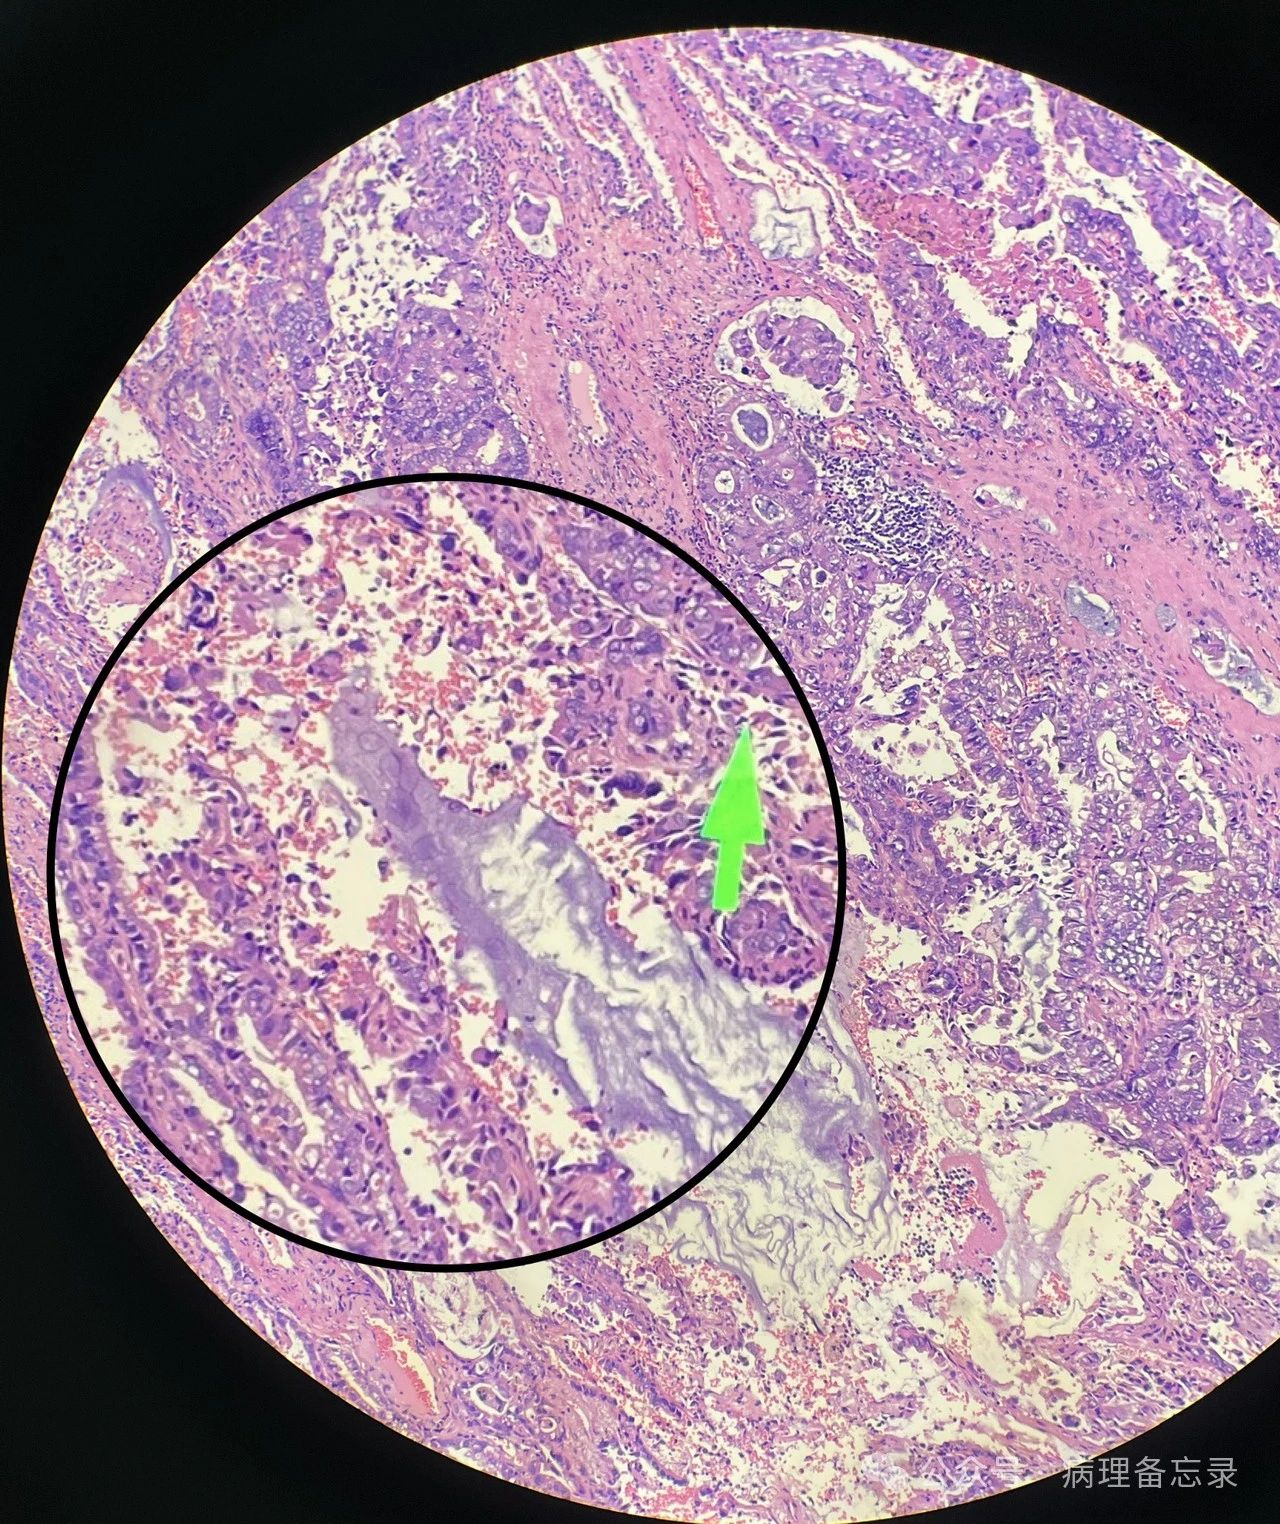

贴壁为主,浸润成分≤5mm(黑色:贴壁型    红色:腺泡型)

腺泡型,肿瘤浸润间质有促纤维反应